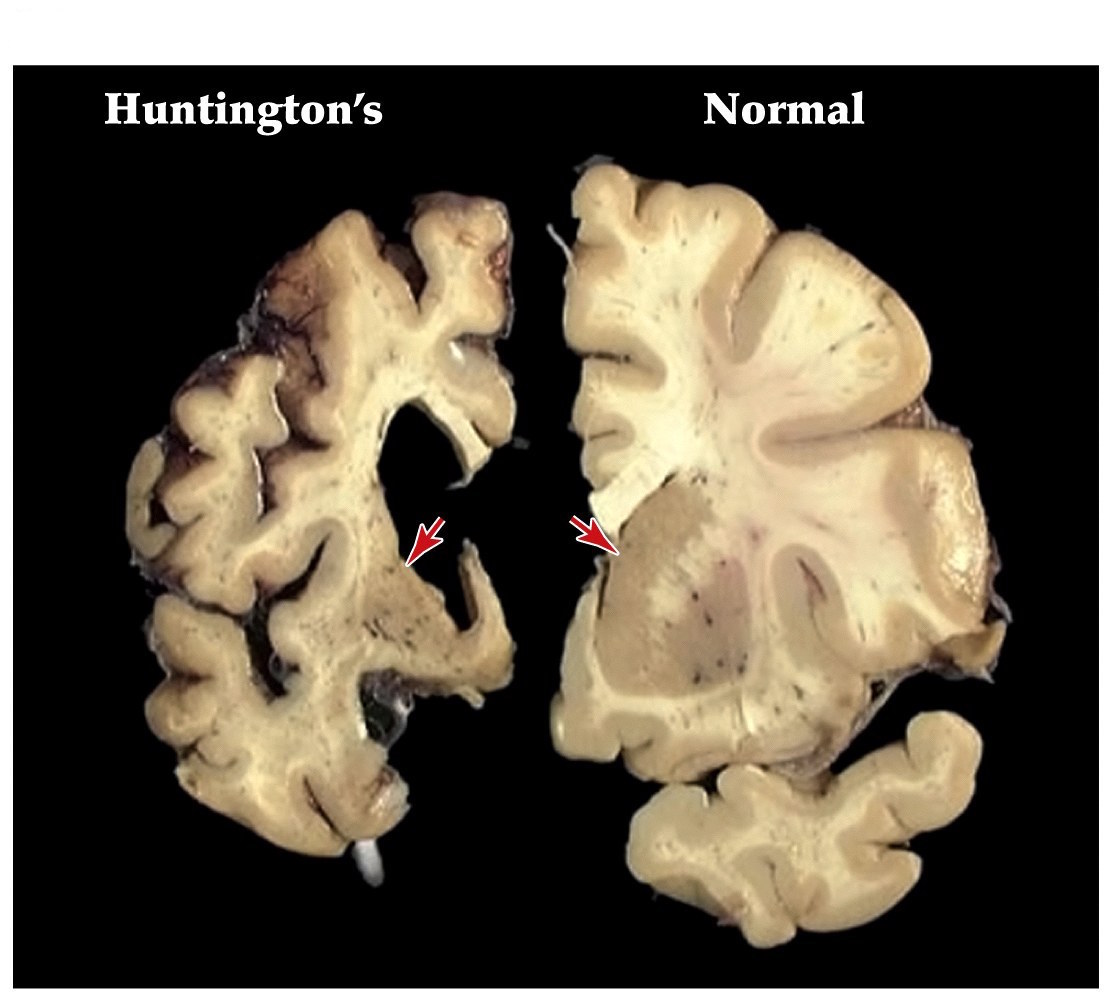

Huntingtons disease

• One of the most common inherited neurological diseases

• Progressive deterioration of the caudate and putamen that project to the GP externa (indirect pathway)

• Leads to a movement disorder consisting of rapid jerky motions with no clear purpose

Neuroscience 5e Fig. 18.9

Note:

• George Huntington, physician long island 1872

• 1 in 10000 people will have Huntington's disease in the US

• death in 10-20 yrs

• autosomal dominant inheritance, chromosome 4. Gene called Huntingtin

• if disease begins in childhood rigidity, seizures, dementia, and rapid progressive course can ensue

• atrophy of striatum is pronounced. Some associated degeneration of frontal and temporal cortices

Function of huntingtin gene product unclear. Null expression in mice lethal

• Dominantly inherited strikes around midlife

• Patients develop depression, mood swings, and abnormal movements (striatum)

• Caused by alterations in a single gene that encodes the huntingtin protein

• Huntingtin protein has an expansion of a CAG trinucleotide repeat, resulting in an extended polyglutamine repeat. Leads to aggregation of proteins and cell death

15-34 cytosine-adenine-guanine (CAG) DNA repeats normally, 42-66 in Huntingtin's disease resulting in an unstable triplet repeat in coding region of gene. Polyglutamine